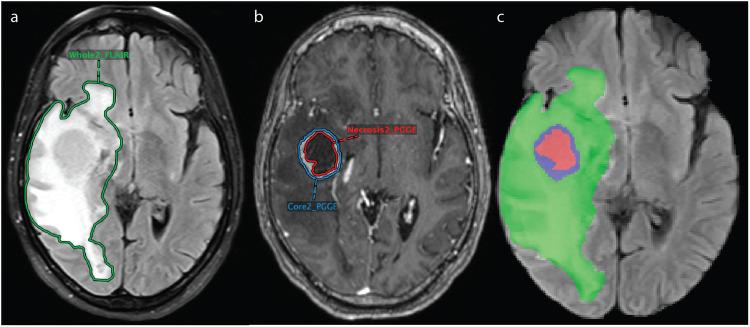

Resection and whole brain radiotherapy (WBRT) are standard treatments for brain metastases (BM) but are associated with cognitive side effects. Stereotactic radiosurgery (SRS) uses a targeted approach with less side effects than WBRT. SRS requires precise identification and delineation of BM. While artificial intelligence (AI) algorithms have been developed for this, their clinical adoption is limited due to poor model performance in the clinical setting. The limitations of algorithms are often due to the quality of datasets used for training the AI network. The purpose of this study was to create a large, heterogenous, annotated BM dataset for training and validation of AI models. We present a BM dataset of 200 patients with pretreatment T1, T1 post-contrast, T2, and FLAIR MR images. The dataset includes contrast-enhancing and necrotic 3D segmentations on T1 post-contrast and peritumoral edema 3D segmentations on FLAIR. Our dataset contains 975 contrast-enhancing lesions, many of which are sub centimeter, along with clinical and imaging information. We used a streamlined approach to database-building through a PACS-integrated segmentation workflow.

切除和全脑放疗(WBRT)是脑转移瘤(BM)的标准治疗方法,但与认知副作用有关。立体定向放射外科(SRS)采用靶向方法,副作用比 WBRT 少。SRS 需要精确识别和描绘 BM。虽然已经开发出用于此目的的人工智能(AI)算法,但由于在临床环境中模型性能不佳,其临床采用受到限制。算法的局限性通常是由于用于训练 AI 网络的数据集中存在的质量问题。本研究的目的是创建一个大型、异质、标注的 BM 数据集,用于训练和验证 AI 模型。我们提出了一个包含 200 名患者的 BM 数据集,这些患者具有预处理 T1、T1 对比后、T2 和 FLAIR MR 图像。该数据集包括 T1 对比后增强和坏死的 3D 分割,以及 FLAIR 上的肿瘤周围水肿的 3D 分割。我们的数据集包含 975 个增强病变,其中许多是亚厘米大小的,同时还包含临床和影像学信息。我们通过与 PACS 集成的分割工作流程,采用简化的方法来构建数据库。